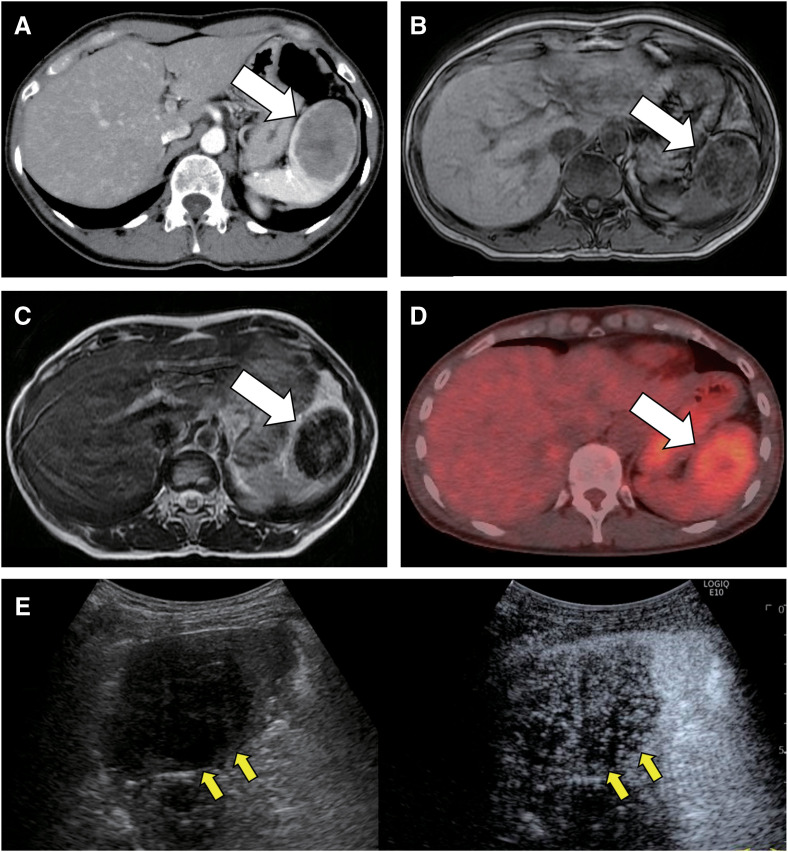

Case presentation: Case 1: A 47-year-old female was found to have a 26 mm tumor in the spleen on abdominal ultrasonography during follow-up for gallbladder polyps. Abdominal computed tomography (CT), magnetic resonance imaging (MRI), and positron emission tomography-CT were performed. EUS-FNA was performed because of the high surgical risk associated with pulmonary hypertension and because hemangioendothelioma, an intermediate malignancy, was suspected. Subsequently, laparoscopic splenectomy was performed, and SANT was diagnosed. Case 2: A 46-year-old female had an incidental detection of a tumor in the spleen on CT. SANT was suspected based on CT and MRI findings. Malignancy could not be completely ruled out owing to the gradual growth of the mass; therefore, the patient was referred to our hospital for surgery. Laparoscopic splenectomy was performed, and SANT was subsequently diagnosed.